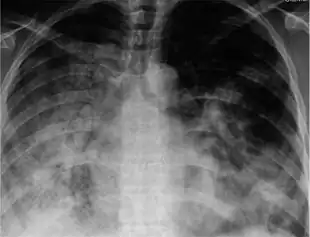

29 yr old with H1N1

There are a number of rapid tests for the flu. One is called a Rapid Molecular Assay, when an upper respiratory tract specimen (mucus) is taken using a nasal swab or a nasopharyngeal swab.[145] It should be done within 3–4 days of symptom onset, as upper respiratory viral shedding takes a downward spiral after that.[146]

Symptomatic infections are usually mild and limited to the upper respiratory tract, but progression to pneumonia is relatively common. Pneumonia may be caused by the primary viral infection or by a secondary bacterial infection. Primary pneumonia is characterized by rapid progression of fever, cough, labored breathing, and low oxygen levels that cause bluish skin. It is especially common among those who have an underlying cardiovascular disease such as rheumatic heart disease. Secondary pneumonia typically has a period of improvement in symptoms for 1–3 weeks[30] followed by recurrent fever, sputum production, and fluid buildup in the lungs,[25] but can also occur just a few days after influenza symptoms appear.[30] About a third of primary pneumonia cases are followed by secondary pneumonia, which is most frequently caused by the bacteria Streptococcus pneumoniae and Staphylococcus aureus.[24][25]